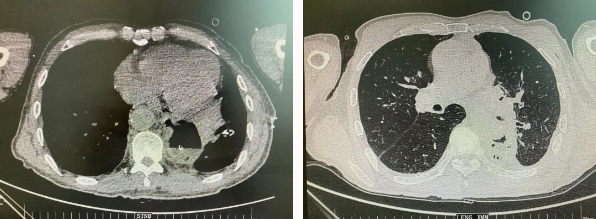

近日,胸科醫(yī)院執(zhí)行院長(zhǎng)李小飛教授帶領(lǐng)胸外科一病區(qū)團(tuán)隊(duì)完成一臺(tái)復(fù)雜胸外科手術(shù):食管癌與肺癌同期手術(shù)。

患者王某不幸同時(shí)患食管癌與左肺癌,病理類(lèi)型系雙源發(fā)腫瘤,食管為鱗癌、肺為腺癌。食管癌和肺癌為胸外科最常見(jiàn)的疾病,但同時(shí)患兩種疾病,十分罕見(jiàn)。家屬輾轉(zhuǎn)多個(gè)醫(yī)院,得知李小飛院長(zhǎng)擅長(zhǎng)胸外科復(fù)雜手術(shù),慕名來(lái)西安國(guó)際醫(yī)學(xué)中心醫(yī)院。

經(jīng)過(guò)李小飛教授、李文海副教授、穆強(qiáng)副主任醫(yī)師團(tuán)隊(duì)積極準(zhǔn)備,排除手術(shù)禁忌;經(jīng)過(guò)全科術(shù)前充分討論,大家認(rèn)為:如果分兩次進(jìn)行手術(shù),另一種疾病勢(shì)必會(huì)受到影響,腫瘤可能進(jìn)展。胸外科手術(shù)對(duì)呼吸循環(huán)影響較大,同期實(shí)施兩個(gè)手術(shù)更要小心謹(jǐn)慎。李小飛教授主持術(shù)前討論,設(shè)計(jì)合理手術(shù)方式,由于食管癌胸腔鏡手術(shù)為右側(cè)入路,但為兼顧左肺癌手術(shù),則采用傳統(tǒng)左開(kāi)胸手術(shù)。

2022年4月25日,由李小飛教授主刀,同期行左側(cè)開(kāi)胸:食管癌根治術(shù) 左肺癌根治術(shù),一次手術(shù)同時(shí)根治兩種惡性腫瘤疾病。經(jīng)過(guò)精細(xì)手術(shù)及術(shù)后管理,患者術(shù)后十天,恢復(fù)良好,進(jìn)食良好,現(xiàn)已出院。